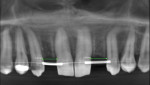

A final CBCT was taken when sufficient space was established, and the positions of the teeth were stabilized for an additional 3 months. The post-orthodontic CBCT image (Figure 4) showed 6.2 mm of space at the No. 7 site and 6.8 mm of space at the No. 10 site to accommodate the impending implants.

Digital imaging and communications in medicine (DICOM) image files from the final CBCT and standard tessellation language (STL) files from the intraoral scan (CEREC Omnicam, Dentsply Sirona, dentsplysirona.com) of the final models were merged using online surgical guide planning software (Passage [version 5.1.12], Anatomage, anatomage.com). A surgical guide was designed and printed for the two implants (Figure 5).

Conservative surgical flaps were made and osteotomies were created using the surgical guide to ensure accurate placement of the 3.2L2 implants (Figure 6). Then, a 0.016-in x 0.022-in NiTi archwire with closed coil springs was used passively for the 3-month integration period (Figure 7). During this time the patient wore the original RPD. Although the success rates of two-stage surgery and one-stage surgery are reported to be equal,12 the clinician opted to use the two-stage approach to allow additional post-orthodontics stabilization time.